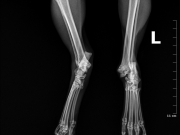

Į veterinarijos kliniką žmonės atvežė automobilio nutrenktą katinuką. Atlikus rentgeną paaiškėjo, kad abi užpakalinės kojos per sąnarius suknežintos į skeveldras. Vienos kojos raiščiai nutraukti. Apžiūrėjusi nuotraukas ir įvertinusi skeveldrinius lūžius chirurgė informavo kad operacija bus itin sudėtinga ir brangi. Vienu metu ji galėtų atlikti tik vienos kojytės operaciją, o po savaitės ar daugiau žiūrint kokia gyvūno būklė galės operuoti antrą. Visa tą laiką katinukas bus klinikos stacionare.

Chirurgė perspėjo kad operacija, gydymas ir pooperacine slauga klinikoje kainuos tikrai pakankamai daug nes užtruks mėnesį ar net daugiau laiko.